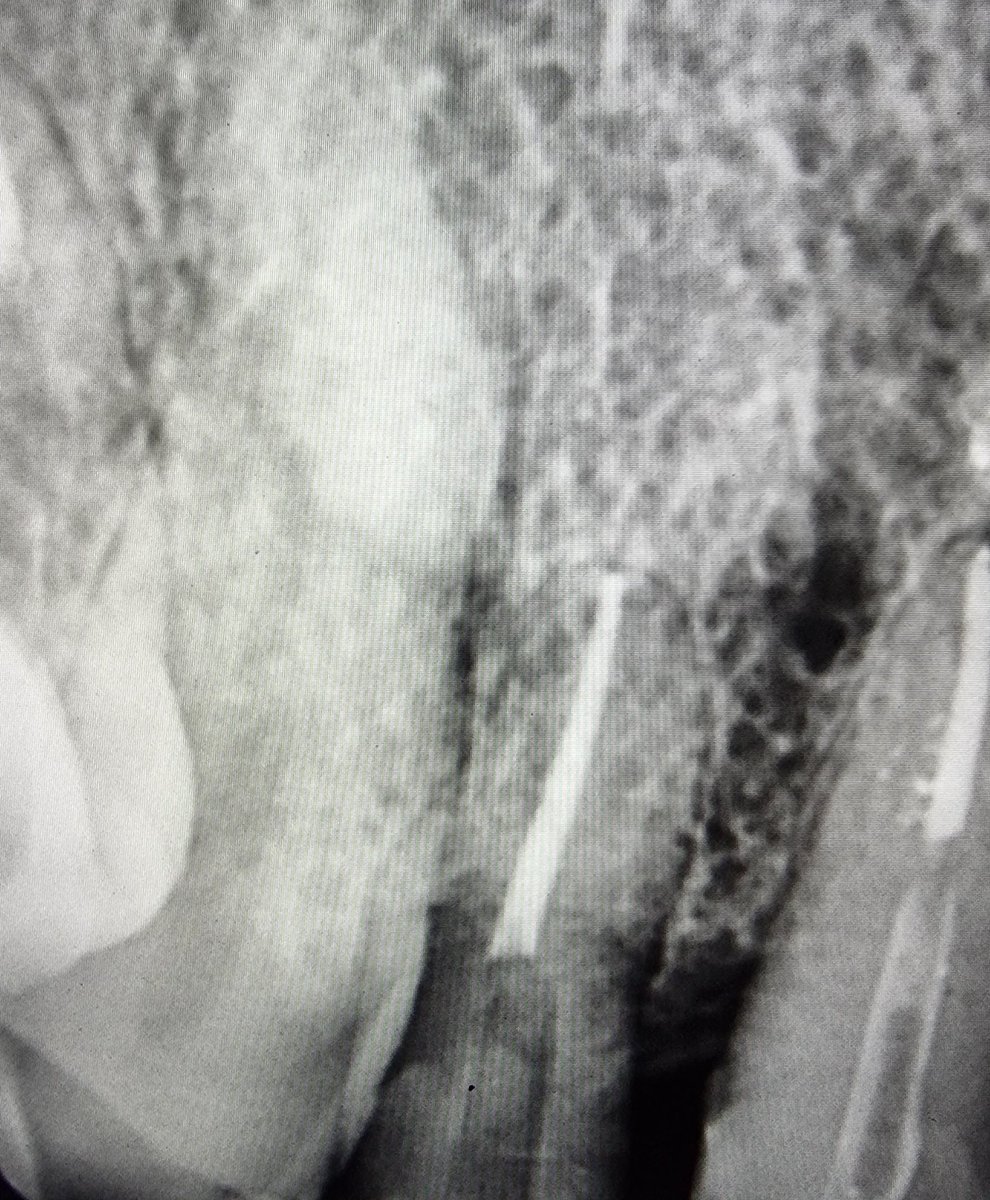

سن معمله علاج عصب وفراغ لم يعمل فيه وتد وتم التركيب عليه فينير وليس تلبيس كامل وهذي اخطاء مركبه

سن معمول له عصب ووتد ومعمول له فينير سيئ وليس تركيب ومتكسر وشكل بشع غير لائق بجودة عمل فاااضحه للاسف وغير مقبوله في تخصصنا

ناب تم فحصه ومركب عليه فينير سيئ السن تكلس وبالفحص السن ميت non vital تم فتح التكلس وعلاج العصب وجميع الاسنان الاماميه بهذا الشكل للاسف ان المريض ذكر لي انها بأرقى أرقى عيادات الرياض وهذا ما استغربته واثبت ذلك بالفعل يعني لا احد يقول المريض ملخبط